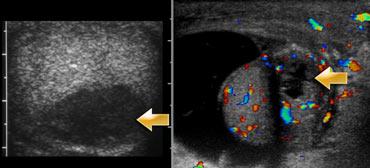

Ở bên trái là hai trường hợp nữa.

Ở ngoài cùng bên trái là một trẻ 10 tháng tuổi bị xoắn tinh hoàn.

Có nhiều lưu lượng máu trong các mô xung quanh tinh hoàn hơn so với trong tinh hoàn, điều này là bất thường, trừ khi trẻ bị viêm mô tế bào.

Ca bên cạnh là một trẻ lớn hơn.

Siêu âm thang xám cho thấy tinh hoàn bất thường.

Vì vậy đây có thể là xoắn tinh hoàn hoặc viêm tinh hoàn, nhưng sự vắng mặt của dòng chảy cho chúng ta biết rằng đây chắc chắn là xoắn tinh hoàn.